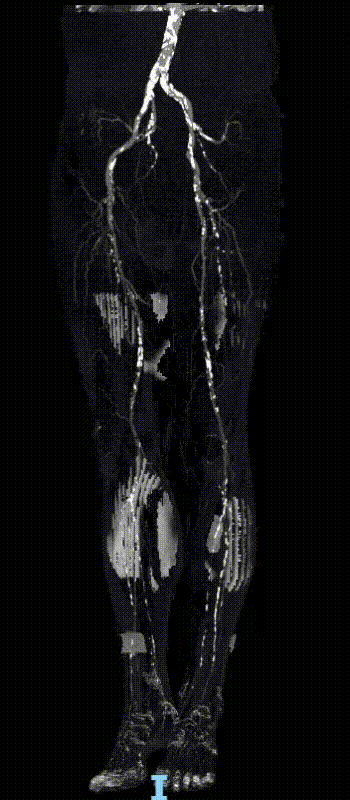

现病史:患者双下肢间歇性跛行5年余,跛距300米。后跛行症状加重伴双足发凉发麻跛距缩短至50米,右侧重、无静息痛、溃疡。下肢CTA提示:双侧股浅动脉重度狭窄近闭塞、右侧腘动脉重度狭窄

右侧:股深动脉重度狭窄,远段闭塞可能;股浅动脉、腘动脉重度狭窄近闭塞;胫后动脉起始重度狭窄,余段闭塞;胫前动脉闭塞

左侧:股深、股浅动脉重度狭窄;腘动脉重度狭窄;胫后动脉闭塞;胫前动脉起始段及远段重度狭窄,余段闭塞可能

股浅动脉重度狭窄伴环周钙化